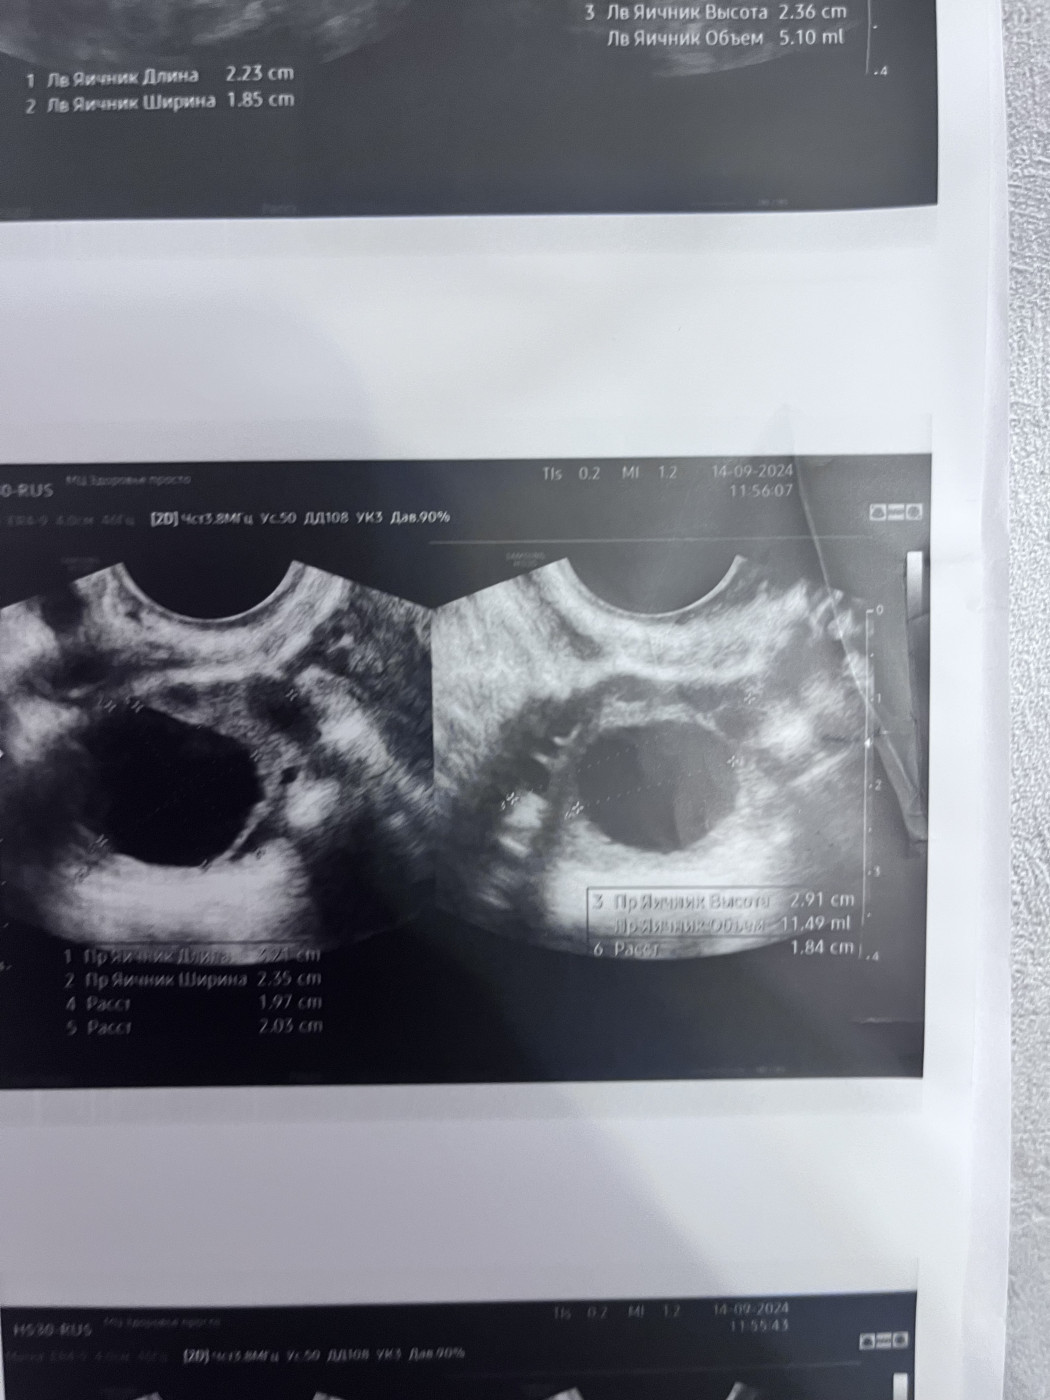

Поставили диагноз полип эндометрияНа 21 дне менструального цикла врач на узи увидела полип. Прикрепляю фото |

После менструального цикла назначили повторное узи, чтобы убедиться полип ли это. Также делала узи через месяц, 11 дней цикла. |

Также посмотрите снимки год назад, там все было хорошо. Спасибо Вам большое заранее |